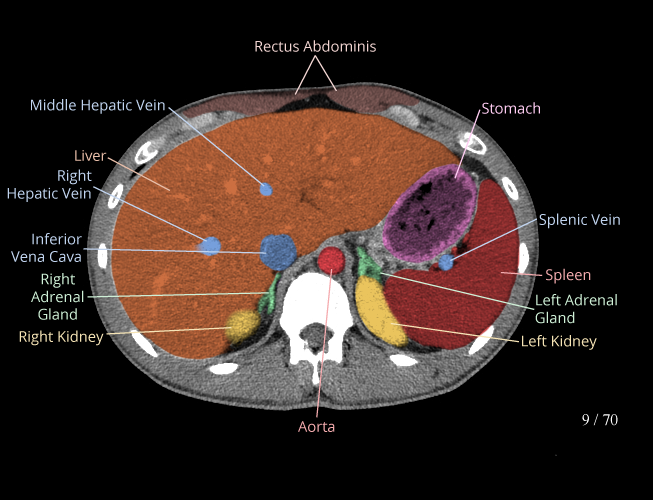

Body

Covers abdominal CT anatomy.